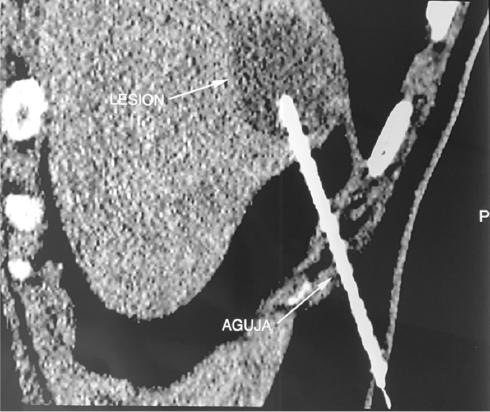

Se decide realizar una tomografía computada (TC) simple y con doble contraste, encontrando engrosamiento en el tercio distal del esófago y en la unión gastroesofágica. En el segmento VII del hígado se observa una lesión nodular de 49 mm, de bordes regulares, definidos, homogéneos, con densidad en fase simple de 15-35 UH (Fig. 1), y el resto del estudio sin alteraciones. Debido a los resultados de la TC, se realiza biopsia percutánea del tumor hepático (Fig. 2), que reporta tumor neuroendocrino moderadamente diferenciado de grado 2, CK7 negativo, CK20 negativo, CEA negativo, HEP-PAR1 negativo, sinaptofisina positivo, cromogranina A positivo y KI67 positivo (5%).

Figura 2 Biopsia percutánea. Las flechas señalan la lesión hepática circunscrita y la aguja utilizada para la toma de biopsia.